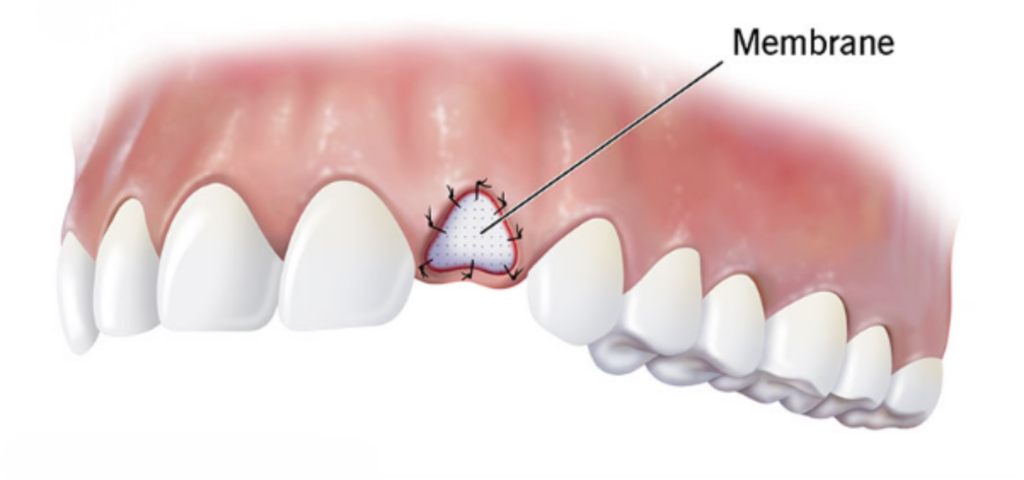

Sinüs Lifting ve Kemik Greft Uygulamaları

Periodontoloji Uygulamaları